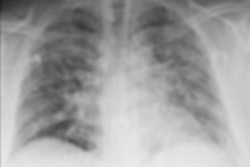

Artificial intelligence (AI) firm DarwinAI has received $750,000 from Lockheed Martin to support the development of its COVID-Net initiative, which aims to utilize AI to diagnose COVID-19 on chest radiographs.

The funds will be used to operationalize the project to make it accessible to clinicians and healthcare professionals, according to the company. These steps will include creating a front-end user interface to simplify ease-of-use as well as integrating the software with PACS, DarwinAI said.